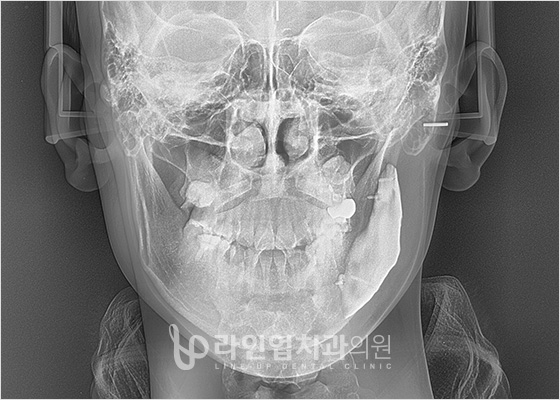

치료전 Before

치료후 After